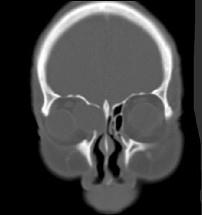

问题 女性,38岁,右侧眼球运动障碍伴眼球突出4个多月,CT扫描如图,请选择正确的描述和答案 ( )

选项 A、考虑为右侧筛窦黏液囊肿 B、考虑为筛窦癌 C、囊性肿块向右侧眼眶内突入,压迫内直肌 D、右侧眶内壁呈受压变薄、断裂 E、右侧筛窦内可见囊性肿块影,边缘光整

答案 ACDE